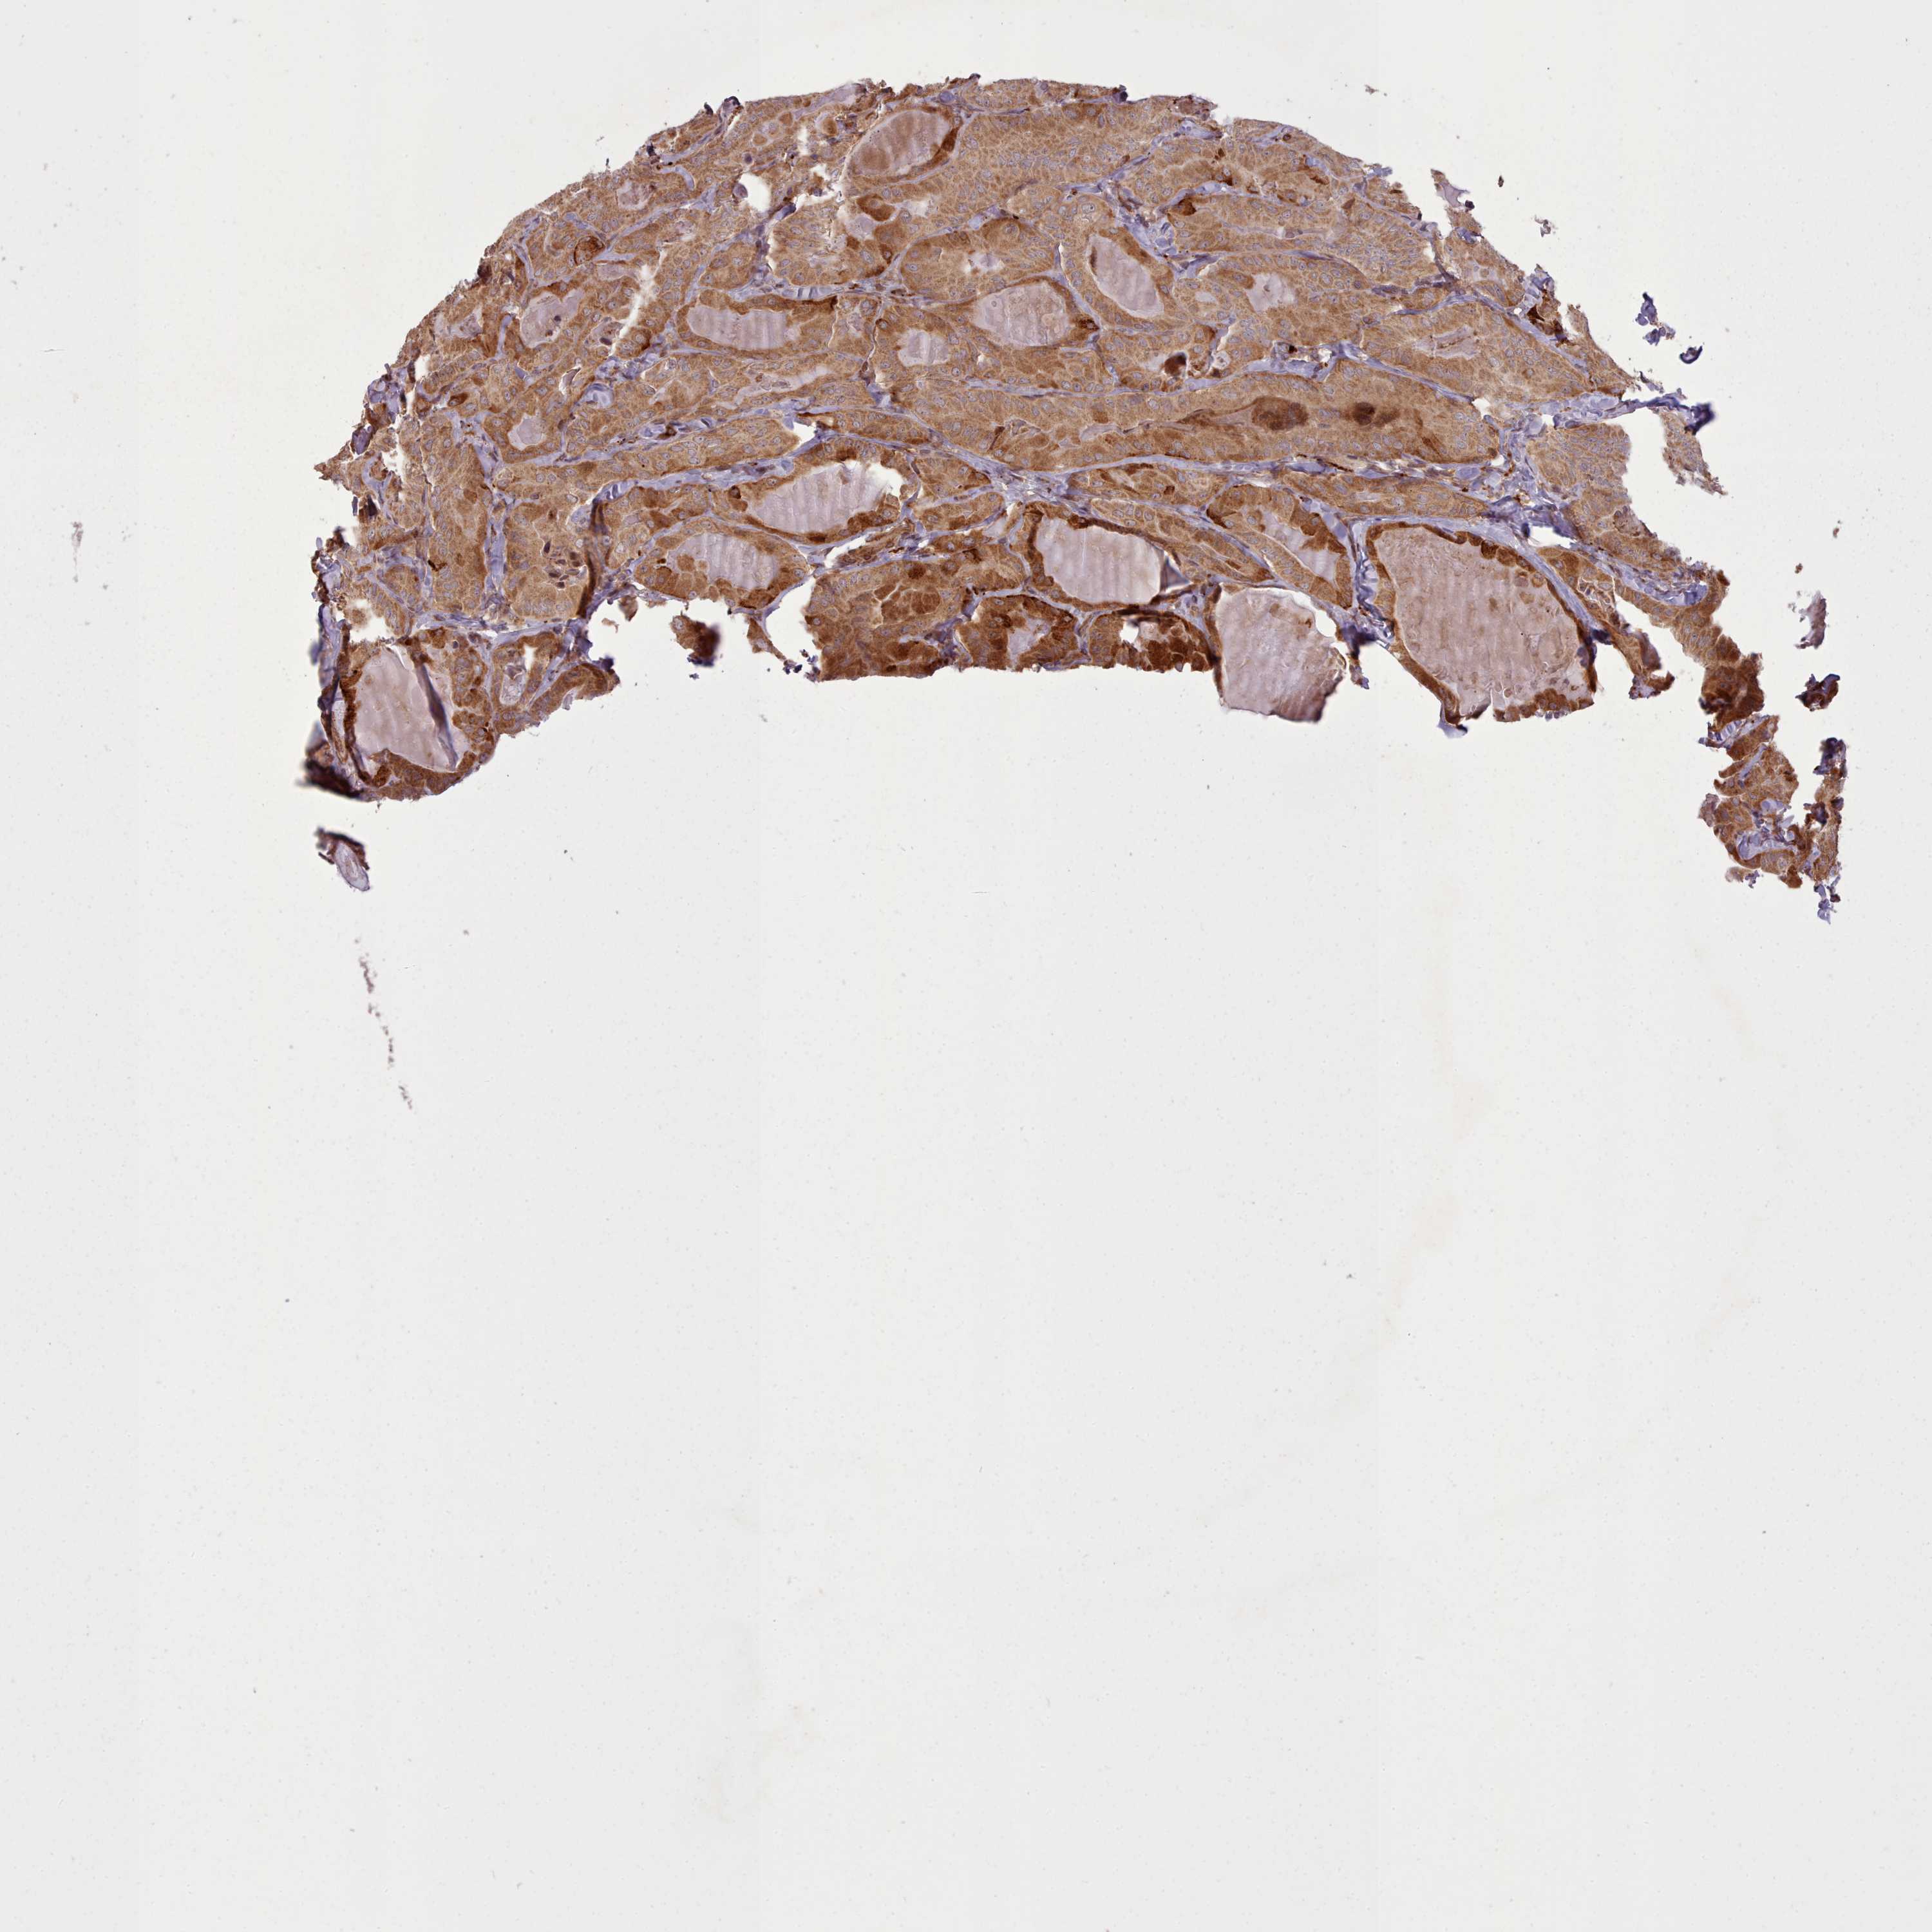

THYROID CANCER - Protein expressioni

A mouse-over function shows sample information and annotation data. Click on an image to view it in a full screen mode. Samples can be filtered based on level of antibody staining by selecting one or several of the following categories: high, medium, low and not detected. The assay and annotation is described here.

Note that samples used for immunohistochemistry by the Human Protein Atlas do not correspond to samples in the TCGA dataset.

Antibody stainingi

Antibody staining in the annotated cell types in the current human tissue is reported as not detected, low, medium, or high, based on conventional immunohistochemistry profiling in selected tissues. This score is based on the combination of the staining intensity and fraction of stained cells.

Each image is clickable and will lead to virtual microscopy that enables deeper exploration of all samples and also displays staining intensity scores, fraction scores and subcellular localization as well as patient and tissue information for each sample.

Antibody HPA051382

Staining

High

Medium

Low

Not detected

Intensity

Strong

Moderate

Weak

Negative

Quantity

>75%

75%-25%

<25%

None

Location

Nuclear

Cytoplasmic/membranous

Cytoplasmic/membranous,nuclear

Papillary adenocarcinoma, NOS

Follicular adenoma carcinoma, NOS